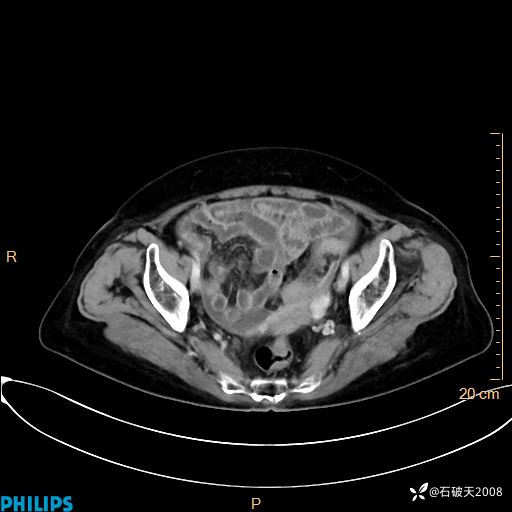

MIP